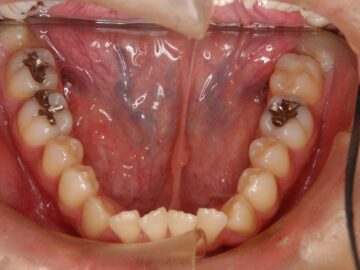

ご相談時

歯ぐきが薄く口唇がわずかに突出しているため、小臼歯抜歯での治療を勧めた。

| 抜歯部位 | 上顎左右測第一小臼歯、下顎左右測第一小臼歯 |

| 治療期間 |

動的治療期間 1年7か月、保定治療期間 1年10か月 |

| 治療のリスク | 歯肉退縮、ブラックトライアングルの出現 |